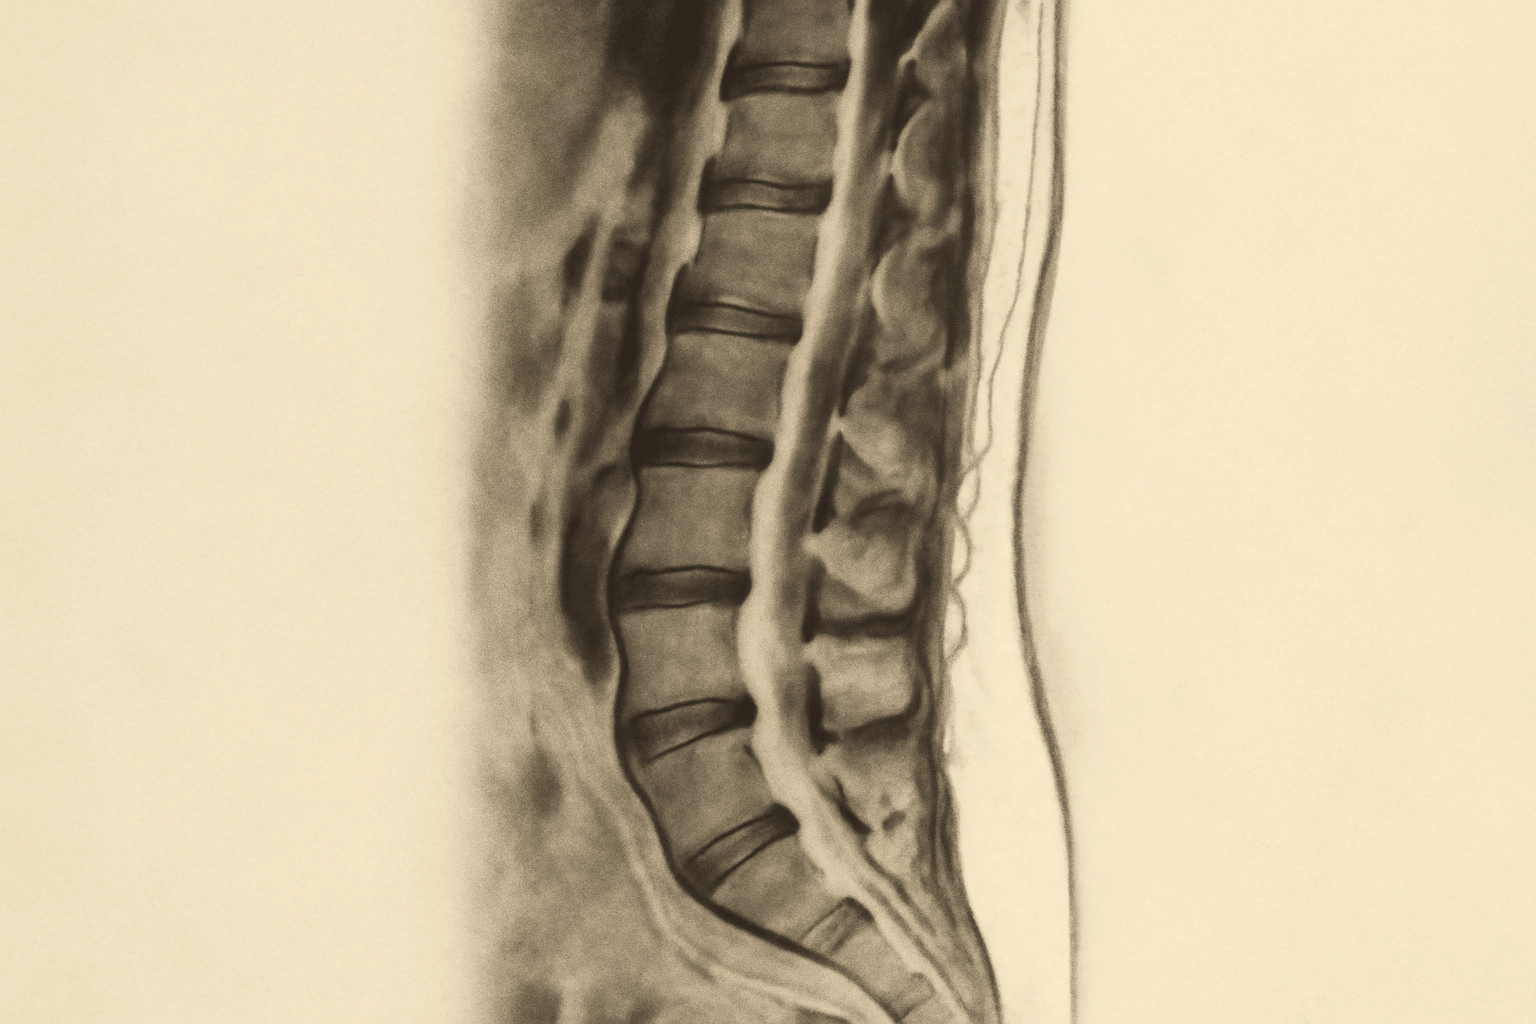

Магнитно-резонансная томография (МРТ) поясничного отдела позвоночника представляет собой важный диагностический метод. Этот вид обследования позволяет получить детальные изображения позвоночника, что помогает специалистам оценить состояние тканей и выявить различные патологии. В современных медицинских центрах используются современные аппараты, обеспечивающие высокое качество снимков и точность диагностики.

Что может выявить МРТ?

Метод позволяет диагностировать ряд заболеваний и состояний. Основные из них включают:

- Грыжи межпозвоночных дисков.

- Спинальные стенозы.

- Травмы.

- Воспалительные процессы.

- Опухоли.

Результаты МРТ поясничного отдела позвоночника Зеленоград предоставляют важную информацию для диагностики и выбора лечения. Основные аспекты, которые могут быть определены на основе полученных изображений, включают:

- Наличие или отсутствие заболеваний. метод позволяет четко визуализировать состояние позвоночника и выявить патологические изменения.

- Степень повреждения. Определяются размеры грыж, степень компрессии нервов и наличие воспалительных процессов.

- Общая анатомия. Исследование позволяет оценить структуру и анатомические изменения в позвоночнике, включая искривления и деформации.

- Расположение образований. Определяется, где именно находятся опухоли или другие аномалии, что имеет значение для хирургического вмешательства.

- Изменения в окружающих тканях. МРТ также помогает выявить состояние мягких тканей, включая мышцы и связки, что важно для комплексной оценки здоровья спины.